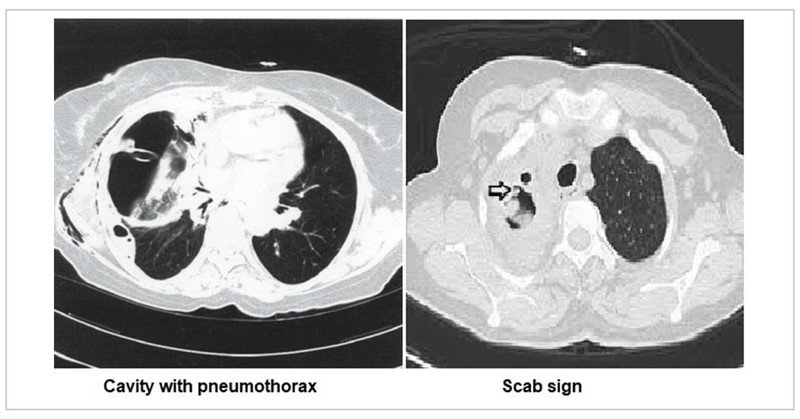

Pulmonary cavity and scab sign

Pulmonary cavity is a thick-walled, air-filled space with or without a fluid level associated with a nodule, mass or consolidation. The spectrum of diseases causing a cavity ranges from infectious, inflammatory, malignant and benign disease processes. While most cavities may be visible on a chest X-ray, cavities that are retrocardiac and apical in nature may be difficult to visualise on a chest radiograph. The cavity may be associated with complications like pneumothorax and hydropneumothorax due to its rupture. The scab sign is characterised by a focal irregular/spiky cavity wall thickening, correlating pathologically with a fibrinopurulent mass and/or blood crust and clinically indicating the site and predisposition to haemoptysis in cavitary pulmonary aspergillosis.